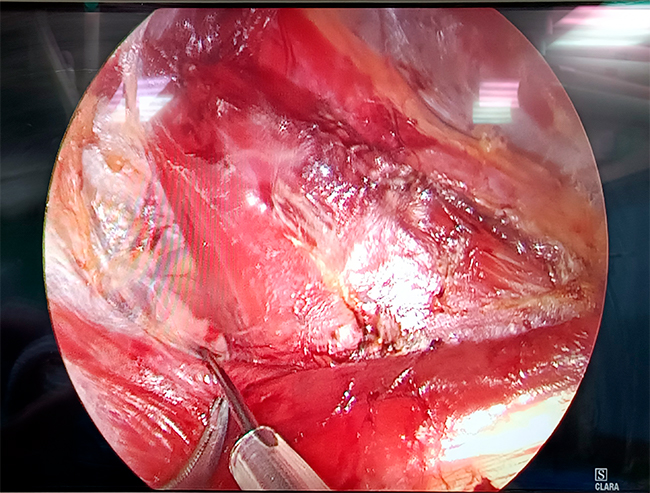

Операция видеоэндохирургическая гемитиреоидэктомия с истмусэктомией справа (удаление одной доли щитовидной железы и ее перешейка) у пациента 40 лет с доброкачественным образованием щитовидной железы проводилась эндоскопическим методом: эндоскопическая техника дает несравнимую с открытыми операциями возможность визуализации всех анатомических структур. В начале операции, приблизившись к нервам, мы проверили «замкнутость цепи»: если нерв отвечает на стимуляцию, на мониторе появляется сигнал, по его амплитуде оценивается степень его травматизации, что позволяет внести коррективы в ход хирургического вмешательства. Так определяют наличие или отсутствие проблем, НЕ связанных с данной операцией. На рис. 2 сигнал от возвратного гортанного нерва. Далее в процессе операции, как я уже отмечал выше, можно в любой момент контролировать сохранность функции нерва.

Визуализация возвратного гортанного нерва Стимуляция гортанного нерва

Стимуляция вагуса

Обратите внимание на то, как расположены троакары (места входа хирургического инструментария): в области подмышечной впадины, плечевого сустава и ареолы справа. Использование такого доступа позволяет обойтись без привычного разреза и последующего послеоперационного рубца на передней поверхности шеи.